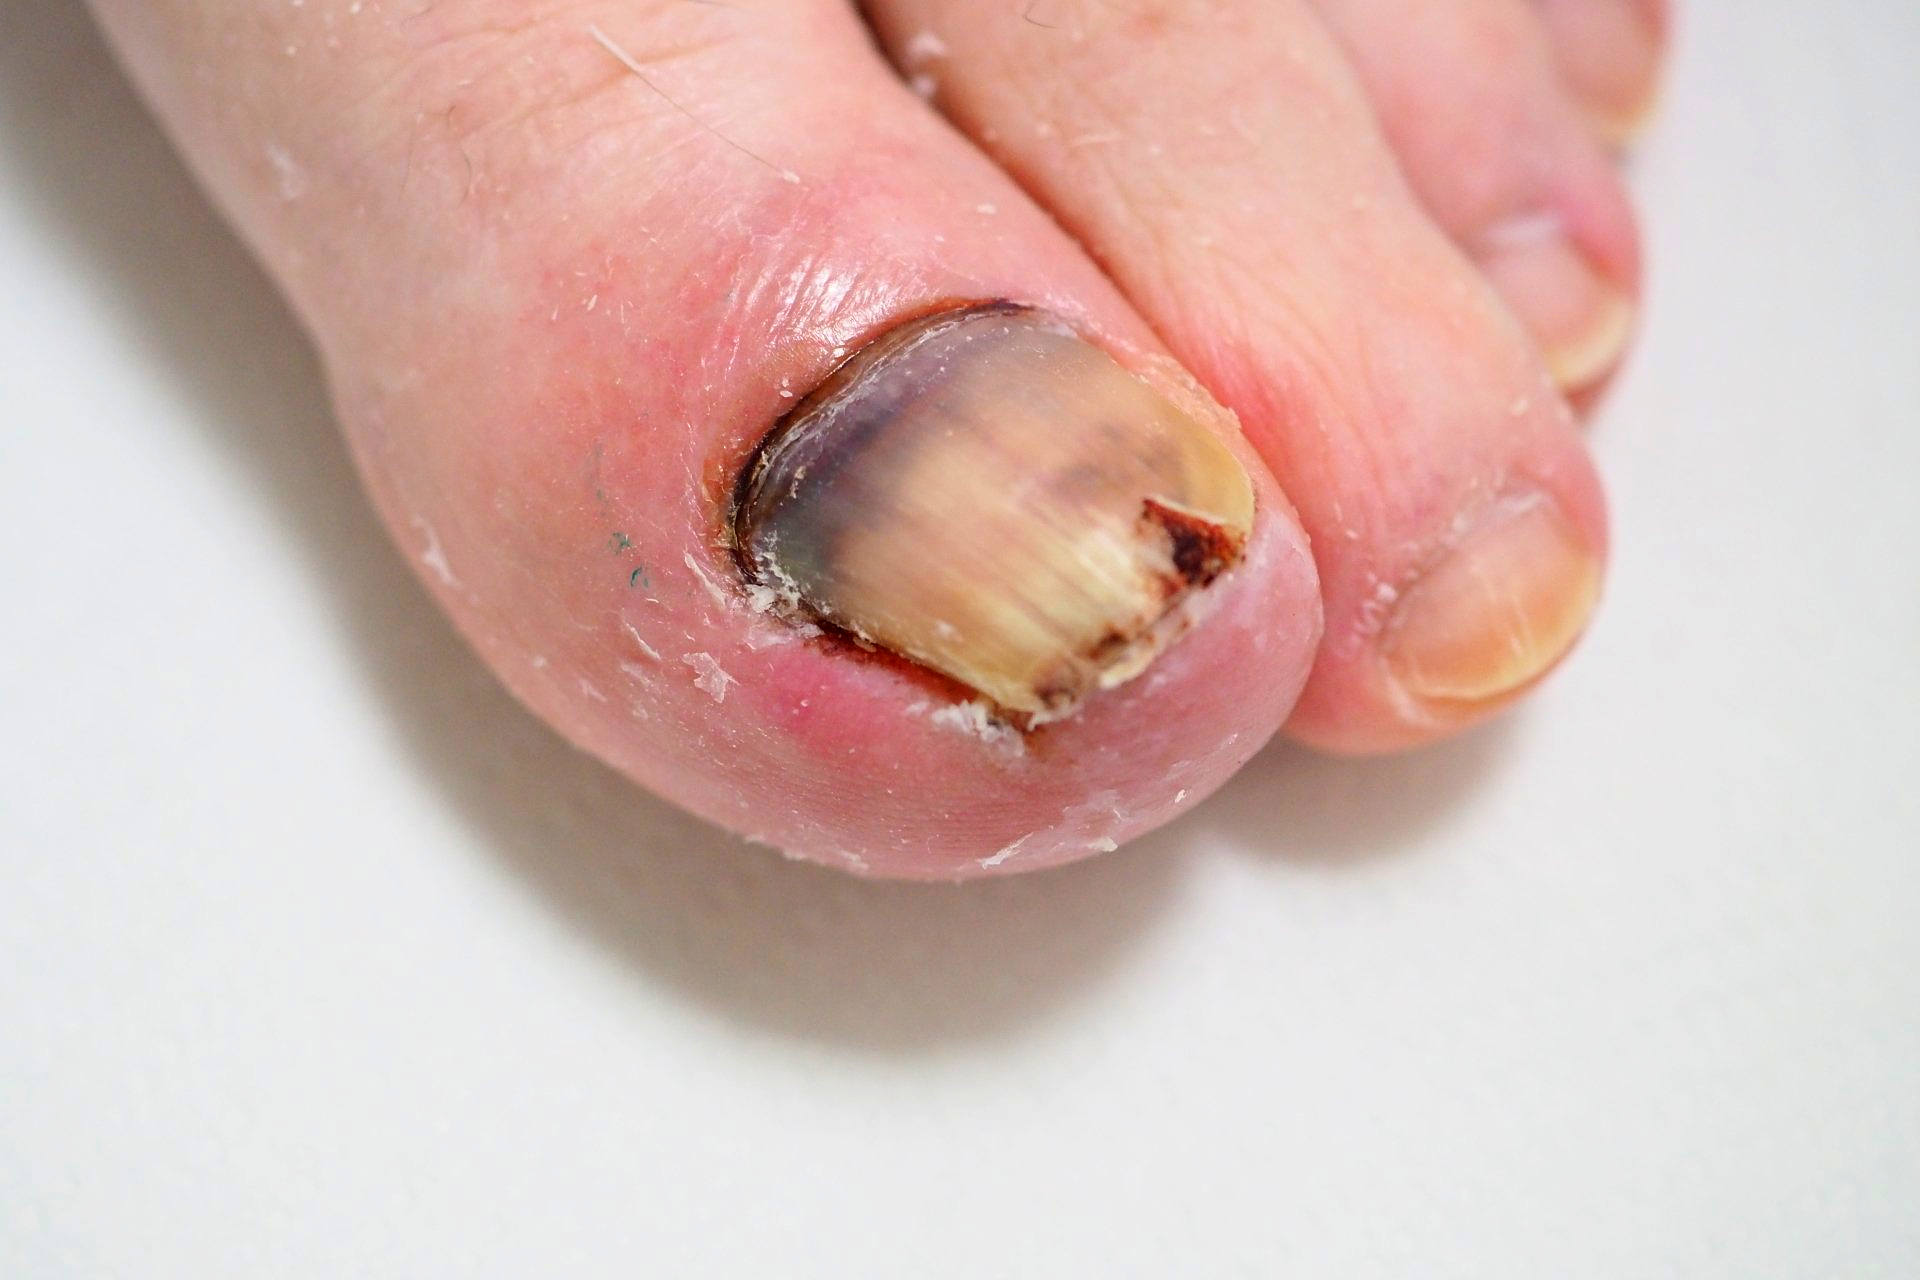

1.) Akutfall am Nagel

👉 Im Folgenden ein Akutfall der besonderen Art:

Kommt nicht sehr oft aber doch immer wieder einmal vor.

🔴 Der Nagelspan kommt bereits DURCH das Weichgewebe.

In Vergrößerung am Monitor auf Bild 2

🔴Bild 3: der geborgene Nagelspan Bild 4: in dieser Position grub sich der Nagel durch das Gewebe